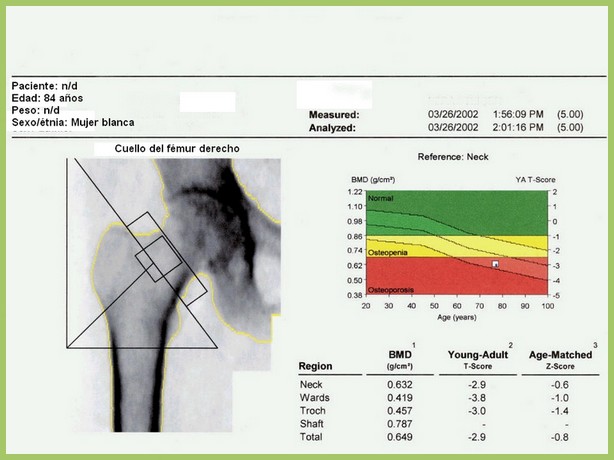

Densitometría ósea: poco cumplimiento de las recomendaciones

06 diciembre 2016